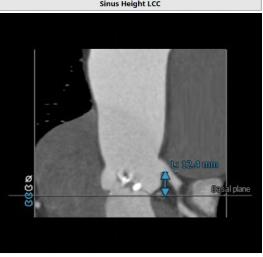

CT:

主动脉瓣Type 0型二叶瓣,瓣叶瓣缘结节样增厚伴中度钙化,开放受限。冠脉高度可。法式窦结构可,心脏角度约52°,左室较小,升主动脉未见明显扩张,右股动脉直径大于5.5mm,可作为主入路。患者为中度钙化的,重度主动脉瓣狭窄,呈鱼嘴型,结合主动脉根部结构,考虑植入Sapien 3瓣膜。

左冠高度

右冠高度